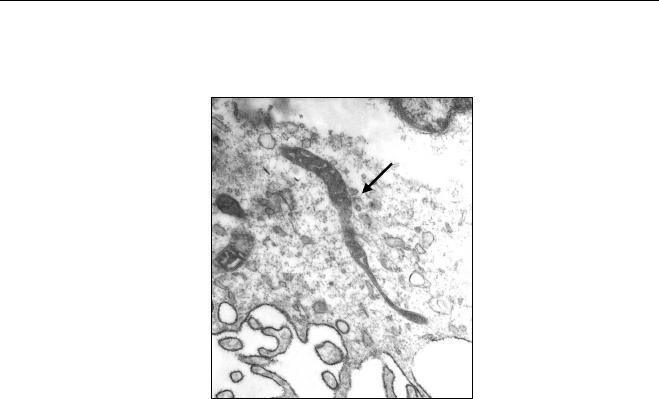

produto final das reações foi analisado em gel de agarose, corado por SYBr

Gold (Invitrogen) e visualizado à trans-iluminação pela ultravioleta.

4.13. Sequenciamento

As amostras que apresentaram positividade nas reações de PCR

foram purificadas com o QIAEX®II Gel Extraction Kit (Qiagen GmbH) e o

sequenciamento foi realizado com o BigDye Terminator Cycle Sequencing

kit, version 3.1 (Applied Biosystems), e analisado pelo ABI Prism 3730 DNA

analyzer (Applied Biosystems). As sequências obtidas foram submetidas à